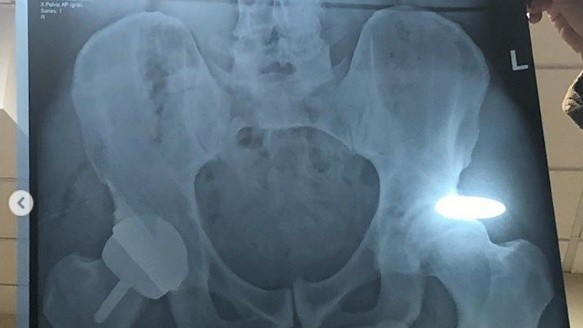

"Ahora tengo una cadera de metal como se puede ver en la segunda foto", escribió en su mensaje, con la imagen de la radiografía.